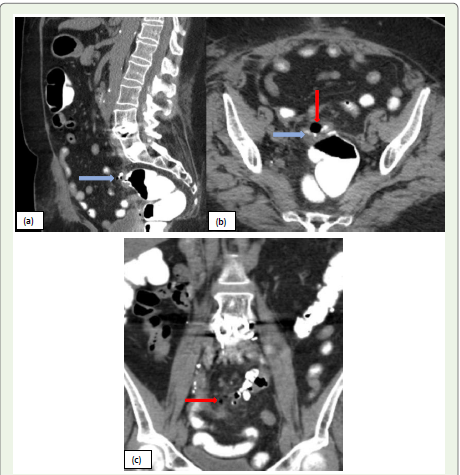

Figure 4: (a, b, c):Sagittal, Axial, and coronal CT images of a 71-year-old

female with complaints of nausea and vomiting. CT scan of the abdomen

and pelvis with oral contrast shows anastomotic sutures in the sigmoid

colon, extra-luminal air loculi around sigmoid anastomosis with minimal extra

luminal oral contrast (blue arrow), consistent with anastomotic leak.